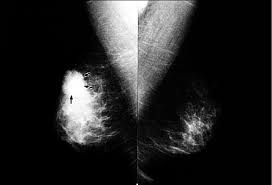

It does not show up on a mammogram and a breast lump is rarely present.

Inflammatory breast cancer has different symptoms. It blocks the lymph vessels in the skin of your breast. It will include a red, inflamed, thickening of the breast. You also may develop red, inflamed skin on the breast. While some women went undiagnosed with breast. Inflammatory breast cancer usually starts with the reddening and swelling of the breast instead of a distinct lump. As these inflammatory breast cancer picture shows, the texture of the breast may change and appear to look dimpled or ridged, like an orange peel. Rapid onset of symptoms (redness, swelling, warmth, itching, skin thickening) are hallmarks of the disease. Mammogram imaging may show skin thickening, but often there is no distinct mass found on physical examination or … Ibc tends to grow in the form of layers or sheets of tissue, which doctors sometimes call nests. But when the lymph vessels become blocked by the breast cancer cells, symptoms begin to appear. A confirmed breast tumor usually requires treatment by surgery and may require chemotherapy, radiation, targeted biological therapy, and/or hormonal therapy. What is inflammatory breast cancer (ibc)?

While some women went undiagnosed with breast. In addition, some types of breast cancer, such as inflammatory breast cancer and paget's disease of the breast, do not usually result in a mass and can easily be overlooked on a mammogram. Inflammatory breast cancer affects breast tissue and can appear unusually dimpled or thick. What does inflammatory breast cancer look like? Meyers (who has not treated cordts).

Inflammatory Breast Cancer Symptoms And Treatment Health Com from imagesvc.meredithcorp.io Breast lesions and chest wall abnormalities 8. A confirmed breast tumor usually requires treatment by surgery and may require chemotherapy, radiation, targeted biological therapy, and/or hormonal therapy. A hallmark sign of inflammatory breast cancer is thickened skin overlying the breast. Unlike traditional forms of breast cancer, inflammatory breast cancers do not develop unusual lumps within the affected breast. But when the lymph vessels become blocked by the breast cancer cells, symptoms begin to appear. The skin looks like the skin of an orange, and may be discolored with painful and itchy breast. What is inflammatory breast cancer (ibc)? Ibc does not usually cause lumps to form in breast tissue.